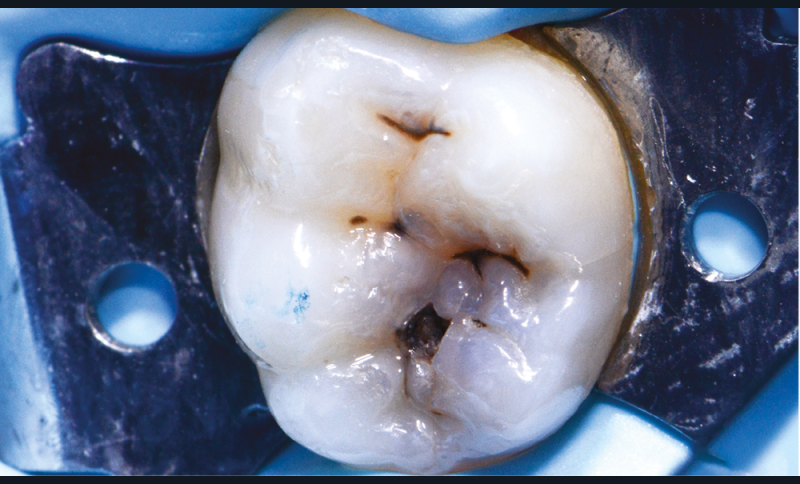

Cliniquement, deux types de lésions carieuses peuvent être observés : des caries actives et des caries chroniques à progression lente.

Dans le cas des caries actives (fig. 1), la surface de l’émail présente une zone opaque blanchâtre ou jaunâtre avec perte de lustre ; elle est ressentie comme rugueuse lorsque la sonde est glissée délicatement le long de la surface. La lésion est située dans une zone de rétention de plaque (puits et sillons, zones à proximité de la gencive et faces proximales sous le point de contact). La dentine sous-jacente devient jaune pâle et ramollie.